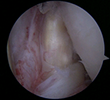

The patient is an elite level pitcher with decreased internal rotation, posterior labral fraying, and infraspinatus rotator cuff symptoms. His posterior labrum has become calcified on xrays and he has non-displaced posterior labral tearing on MRA. He has failed physical therapy and continued posterior impingement symptoms with throwing/pitching. At the time of shoulder arthroscopy, his posterior labrum was frayed (photo 1) and this was debrided. The undersurface of his infraspinatus is inflamed but not torn (photo 2). The posterior capsule is inflamed, stiff, and thickened (photo 3). The posterior capsule is released with the use of an arthroscopic scissors (photo 4). After release, the patients range of motion returned to that of the other side. He returned to pitching and went on to enter the MLB Draft.